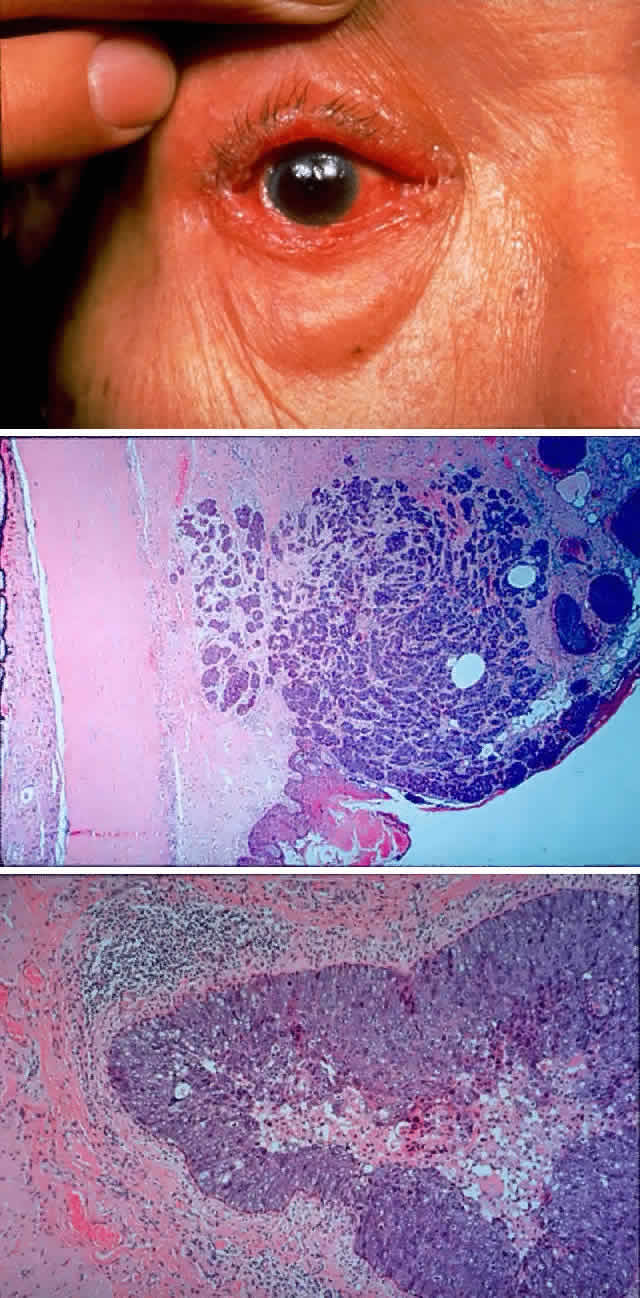

Sebaceous carcinoma has achieved a notorious reputation because it can be difficult to diagnose correctly in the early stages. Clinically, the tumor may masquerade as a chronic chalazion, blepharoconjunctivitis, basal cell carcinoma, keratoconjunctivitis, or very rarely as a primary orbital tumor. Another cause for confusion has been pathologic misdiagnosis of sebaceous carcinoma, most commonly being mistaken for basal cell carcinoma or squamous cell carcinoma. Increasing awareness of the characteristic presentation, along with earlier and more accurate clinical and pathologic diagnosis, has decreased the mortality associated with this tumor. The blepharoconjunctivitis associated with this lesion is the result of intraepithelial (pagetoid) spread of sebaceous carcinoma. The usual clinical appearance is a thickening of the conjunctiva associated with frank injection in areas of invasion (Fig. 9). A careful biomicroscopic examination reveals yellowish, plaque-like foci within the affected epithelium.

Fig. 9. A 79-year-old man had been treated for several years for chronic blepharoconjunctivitis. On examination, he had thickening of upper and lower lid margins, diffuse symblepharon, conjunctival thickening, injection, and yellowish plaque-like foci (A). Conjunctival biopsy confirmed invasive sebaceous cell carcinoma, and subtotal exenteration was performed. Tumor invasion along the globe (B) (H & E, × 32) and into muscle (C) (H & E, × 80) was noted.

The incidence of orbital extension varies from 6% to 35% in large series64–66 and is associated with a 70% mortality rate. These tumors have a propensity to spread to the lymphatic system and subsequently to the lung, liver, brain, or skull. Those that extend into the orbit have approximately a 70% association with preauricular, cervical, or submaxillary adenopathy compared with an overall incidence of approximately 19% for all sebaceous gland carcinomas of the lid and adnexa.

The pathologic diagnosis is based on evidence of sebaceous origin. These carcinomas are usually lobular or consist of cords of cells with a varying degree of sebaceous differentiation and infiltration. The degree of differentiation tends to progress from the periphery toward the center of lobules, mimicking the normal pattern of sebaceous glands. Cells that are differentiated have a foamy or vacuolated, slightly basophilic cytoplasm. In contrast, the less differentiated tumors have cells that are more deeply basophilic and anaplastic, and they display more mitotic figures. The peripheral location of the basophilic, less vacuolated cells produces a pattern similar to basal cell carcinoma, but the cells are more anaplastic. Sebaceous carcinomas have a propensity toward pagetoid spread, invading the basal layers of skin and mucous membranes in a radial fashion. These tumors characteristically contain fat; thus, frozen sections and fat stains are useful in diagnosis and at the time of controlled resection.